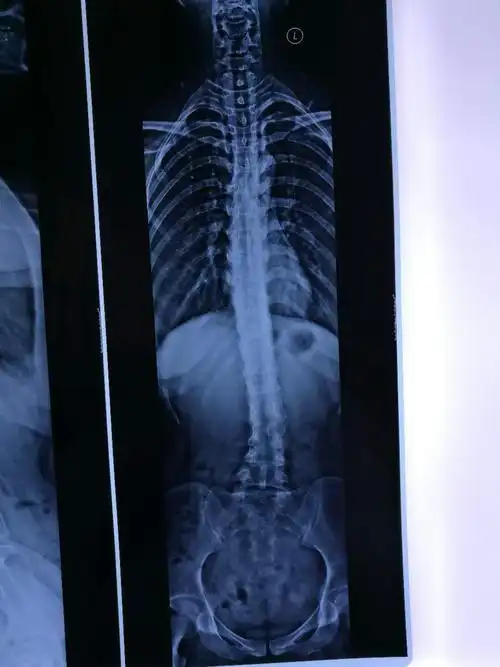

先天腰间盘突出,脊柱达到45度弯曲的人有多痛苦?

25岁女性,腰椎变弯情况已经有1-2年了,现在直不起腰来,有疼痛感,请

腰椎间盘突出合并腰椎管狭窄症

巨大腰椎间盘脱出,非得手术?颊针疗法显神威!

腰椎间盘突出超微针刀治疗验案